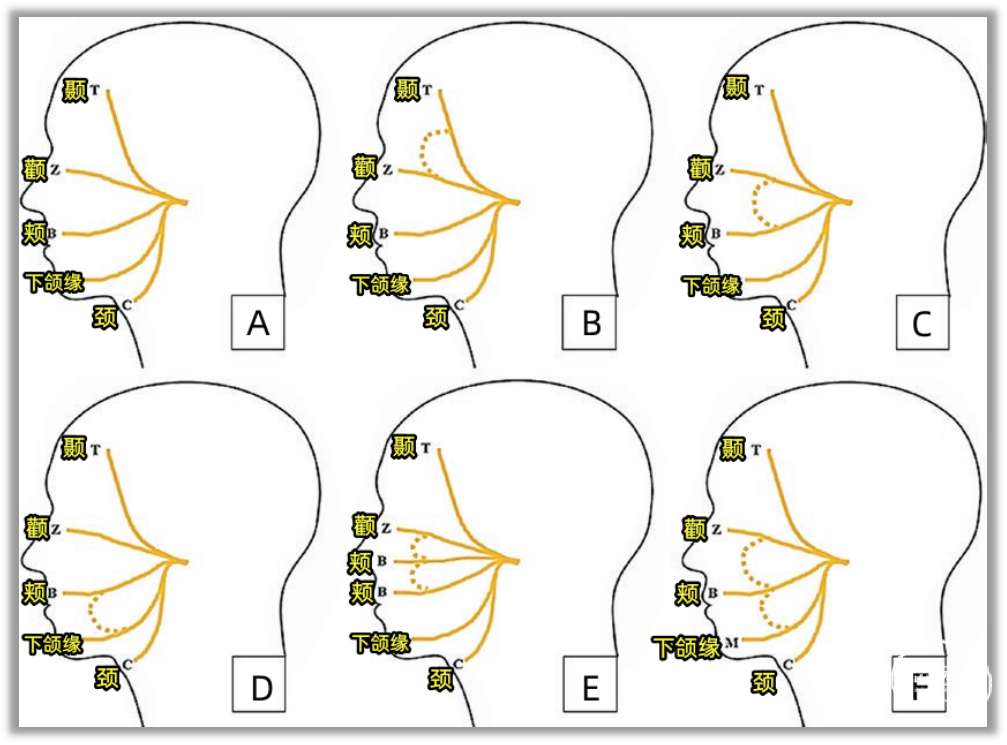

▼基本原理

由于在HFS中面神经功能亢进,刺激面神经的一个分支(下图,刺激颧支或颞支)不仅诱发一个来自该条分支支配肌肉(下图,眼轮匝肌)的反应波,刺激还会逆行经面神经纤维传入,在REZ区经过责任血管壁交感神经桥接或神经纤维之间短路(目前尚无定论),传导到其他面神经分支纤维(下图,下颌缘支),在其他面部肌肉(下图,颏肌)记录到一个相对延迟10ms的的反应波(LSR 下图)。

减压后(下图),只能记录到来自被刺激分支支配肌肉(下图,眼轮匝肌)的反应波,刺激无法在REZ区传导到其他面神经分支纤维,LSR会消失(下图)。

▼操作方法

刺激电极放置在面神经颧支(或颞支)处(颧支刺激位置是将电极放置在耳屏和眼外眦连线的中点处)。

记录电极放置在的颏肌 和 眼轮匝肌处(皮下0.5~1.0cm)。